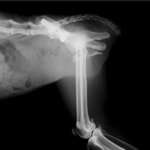

症例3:キルシュナーワイヤーのピンニングによる整復

ペルシャ猫 11ヶ月齢 雄

他院にて左大腿骨遠位の成長板骨折(salter-harrisⅠ型)が認められており、治療相談を目的として来院。当院にて、キルシュナーワイヤーを用いたピンニングにより骨折部位の整復を行いました。術後の経過は良好で、現在も経過観察中です。

術前レントゲン

術後レントゲン

機器

Arthrex社のターゲティングデバイスを用いてピンニングの位置を調整することで、確実な固定を行っています。当院ではこの手術器具以外にも、人の手術にも使用される様々な器具を導入し、手術精度を高め、また医療メーカーと新しい器具の開発、試作にも取り組んでおります。